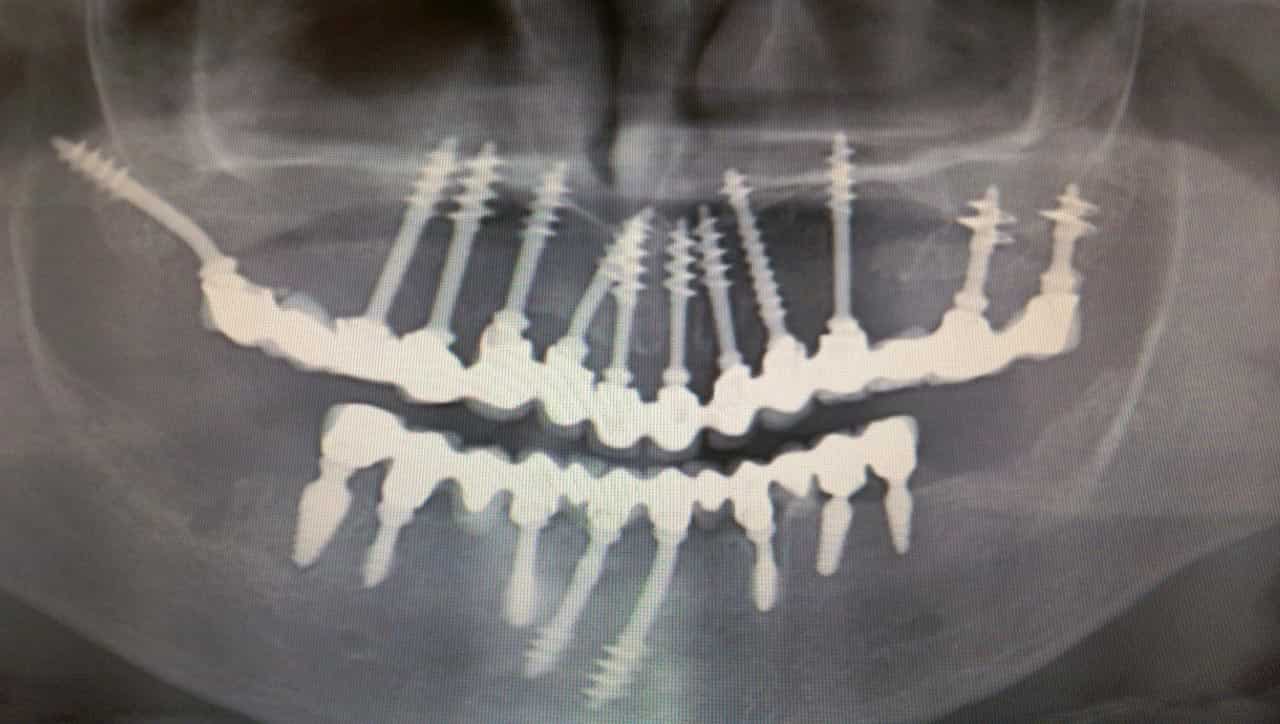

Fog implantátum

Az életre szóló megoldások sarkalatos pontja a minőség. Ha valamiért nagyobb összeget fizetünk ki, érthető, hogy színvonalas eredményekre vágyunk. Az azonnal terhelhető fog implantátum vonatkozásában egészen biztosan nem fogunk csalódni! Mt is vár egészen pontosan a páciens, ha „fogas” kérdéssel keresi fel a kiszemelt szájsebészeti rendelőt?

Nos, legyen szó csupán egy-két fog pótlásáról, egyszerű foghúzásról, cisztaműtétről vagy az egész fogsor egykori állapotának a visszaállításáról, amit joggal elvárunk, az a felsőkategóriás kiszolgálás és az időtálló eredmény. Mivel senki sem szeret fogorvoshoz járni, érthető, ha nem kívánjuk rendszeresen megismételni a látogatást és olyan végeredményt szeretnénk a magunkénak tudni, ami kiállja az idő próbáját.

Abban az esetben, ha a fog implantátum beültetését és az egyéb fogászati eljárásokat a Dental Center gárdájára bízza, a fentiekben felsoroltak mellé gyors és precíz munkavégzést, modern mágnesterápiás utókezelést is kap, ráadásul nem csillagászati összegekért cserébe.